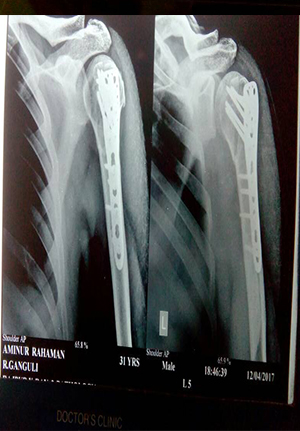

Reduction and internal fixation for proximal humerus fracture

before operation

After operation